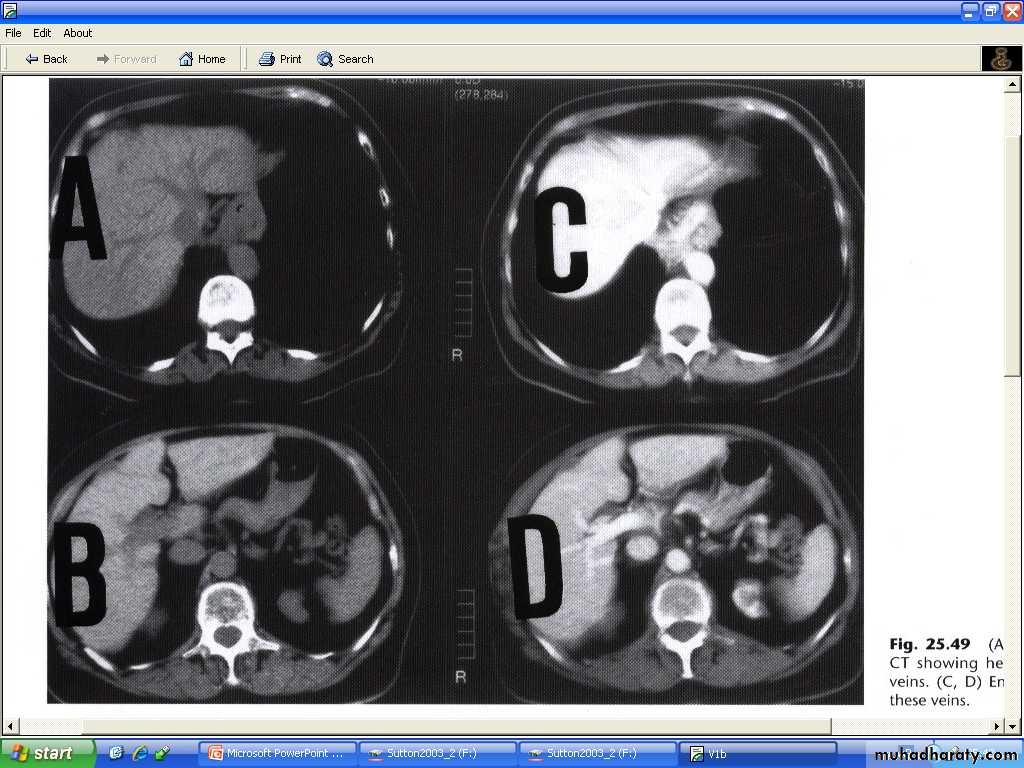

CT

# usually seen as lower density than the contrast enhanced surrounding liver parenchyma.

# intense contrast enhancement some time seen within the tumor or immediately surrounding them- a useful differentiating feature , which is not seen with cysts.

# some metastases ( e.g. carcinoid )are hypervascular and appear as high density areas.